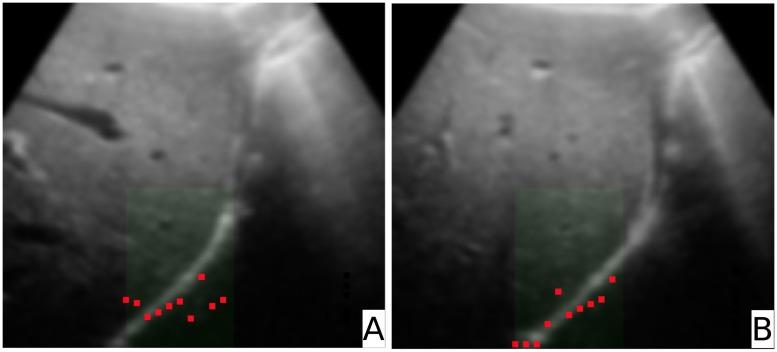

US image registration is an important task e.g. in Computer Aided Surgery. Due to tissue deformation occurring between pre-operative and interventional images often deformable registration is necessary. We present a registration method focused on surface structures (i.e. saliencies) of soft tissues like organ capsules or vessels. The main concept follows the idea of representative landmarks (so called leading points). These landmarks represent saliencies in each image in a certain region of interest. The determination of deformation was based on a geometric model assuming that saliencies could locally be described by planes. These planes were calculated from the landmarks using two dimensional linear regression. Once corresponding regions in both images were found, a displacement vector field representing the local deformation was computed. Finally, the deformed image was warped to match the pre-operative image. For error calculation we used a phantom representing the urinary bladder and the prostate. The phantom could be deformed to mimic tissue deformation. Error calculation was done using corresponding landmarks in both images. The resulting target registration error of this procedure amounted to 1.63 mm. With respect to patient data a full deformable registration was performed on two 3D-US images of the abdomen. The resulting mean distance error was 2.10 ± 0.66 mm compared to an error of 2.75 ± 0.57 mm from a simple rigid registration. A two-sided paired t-test showed a p-value < 0.001. We conclude that the method improves the results of the rigid registration considerably. Provided an appropriate choice of the filter there are many possible fields of applications.